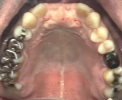

女性Tさん 60代(インプラント)

主訴

上の前歯の部分入れ歯が合わないので、インプラントにしたい。

治療内容

インプラントを4本埋入しました。

所感

骨の厚みが薄かったのですが、X-Guideを用い、正確に埋入することが来ました。

治療後「とてもきれいに出来てうれしかったです。話をしても、空気がもれず良くなりました。もう少し早く治すと良かったと思いました。」と、とても喜んでくださいました。

インプラント4本:¥363,000×4本=¥1,452,000(税込)

Before

インプラント埋入前

義歯を装着したところ

使用していた部分入れ歯

After

インプラント埋入後